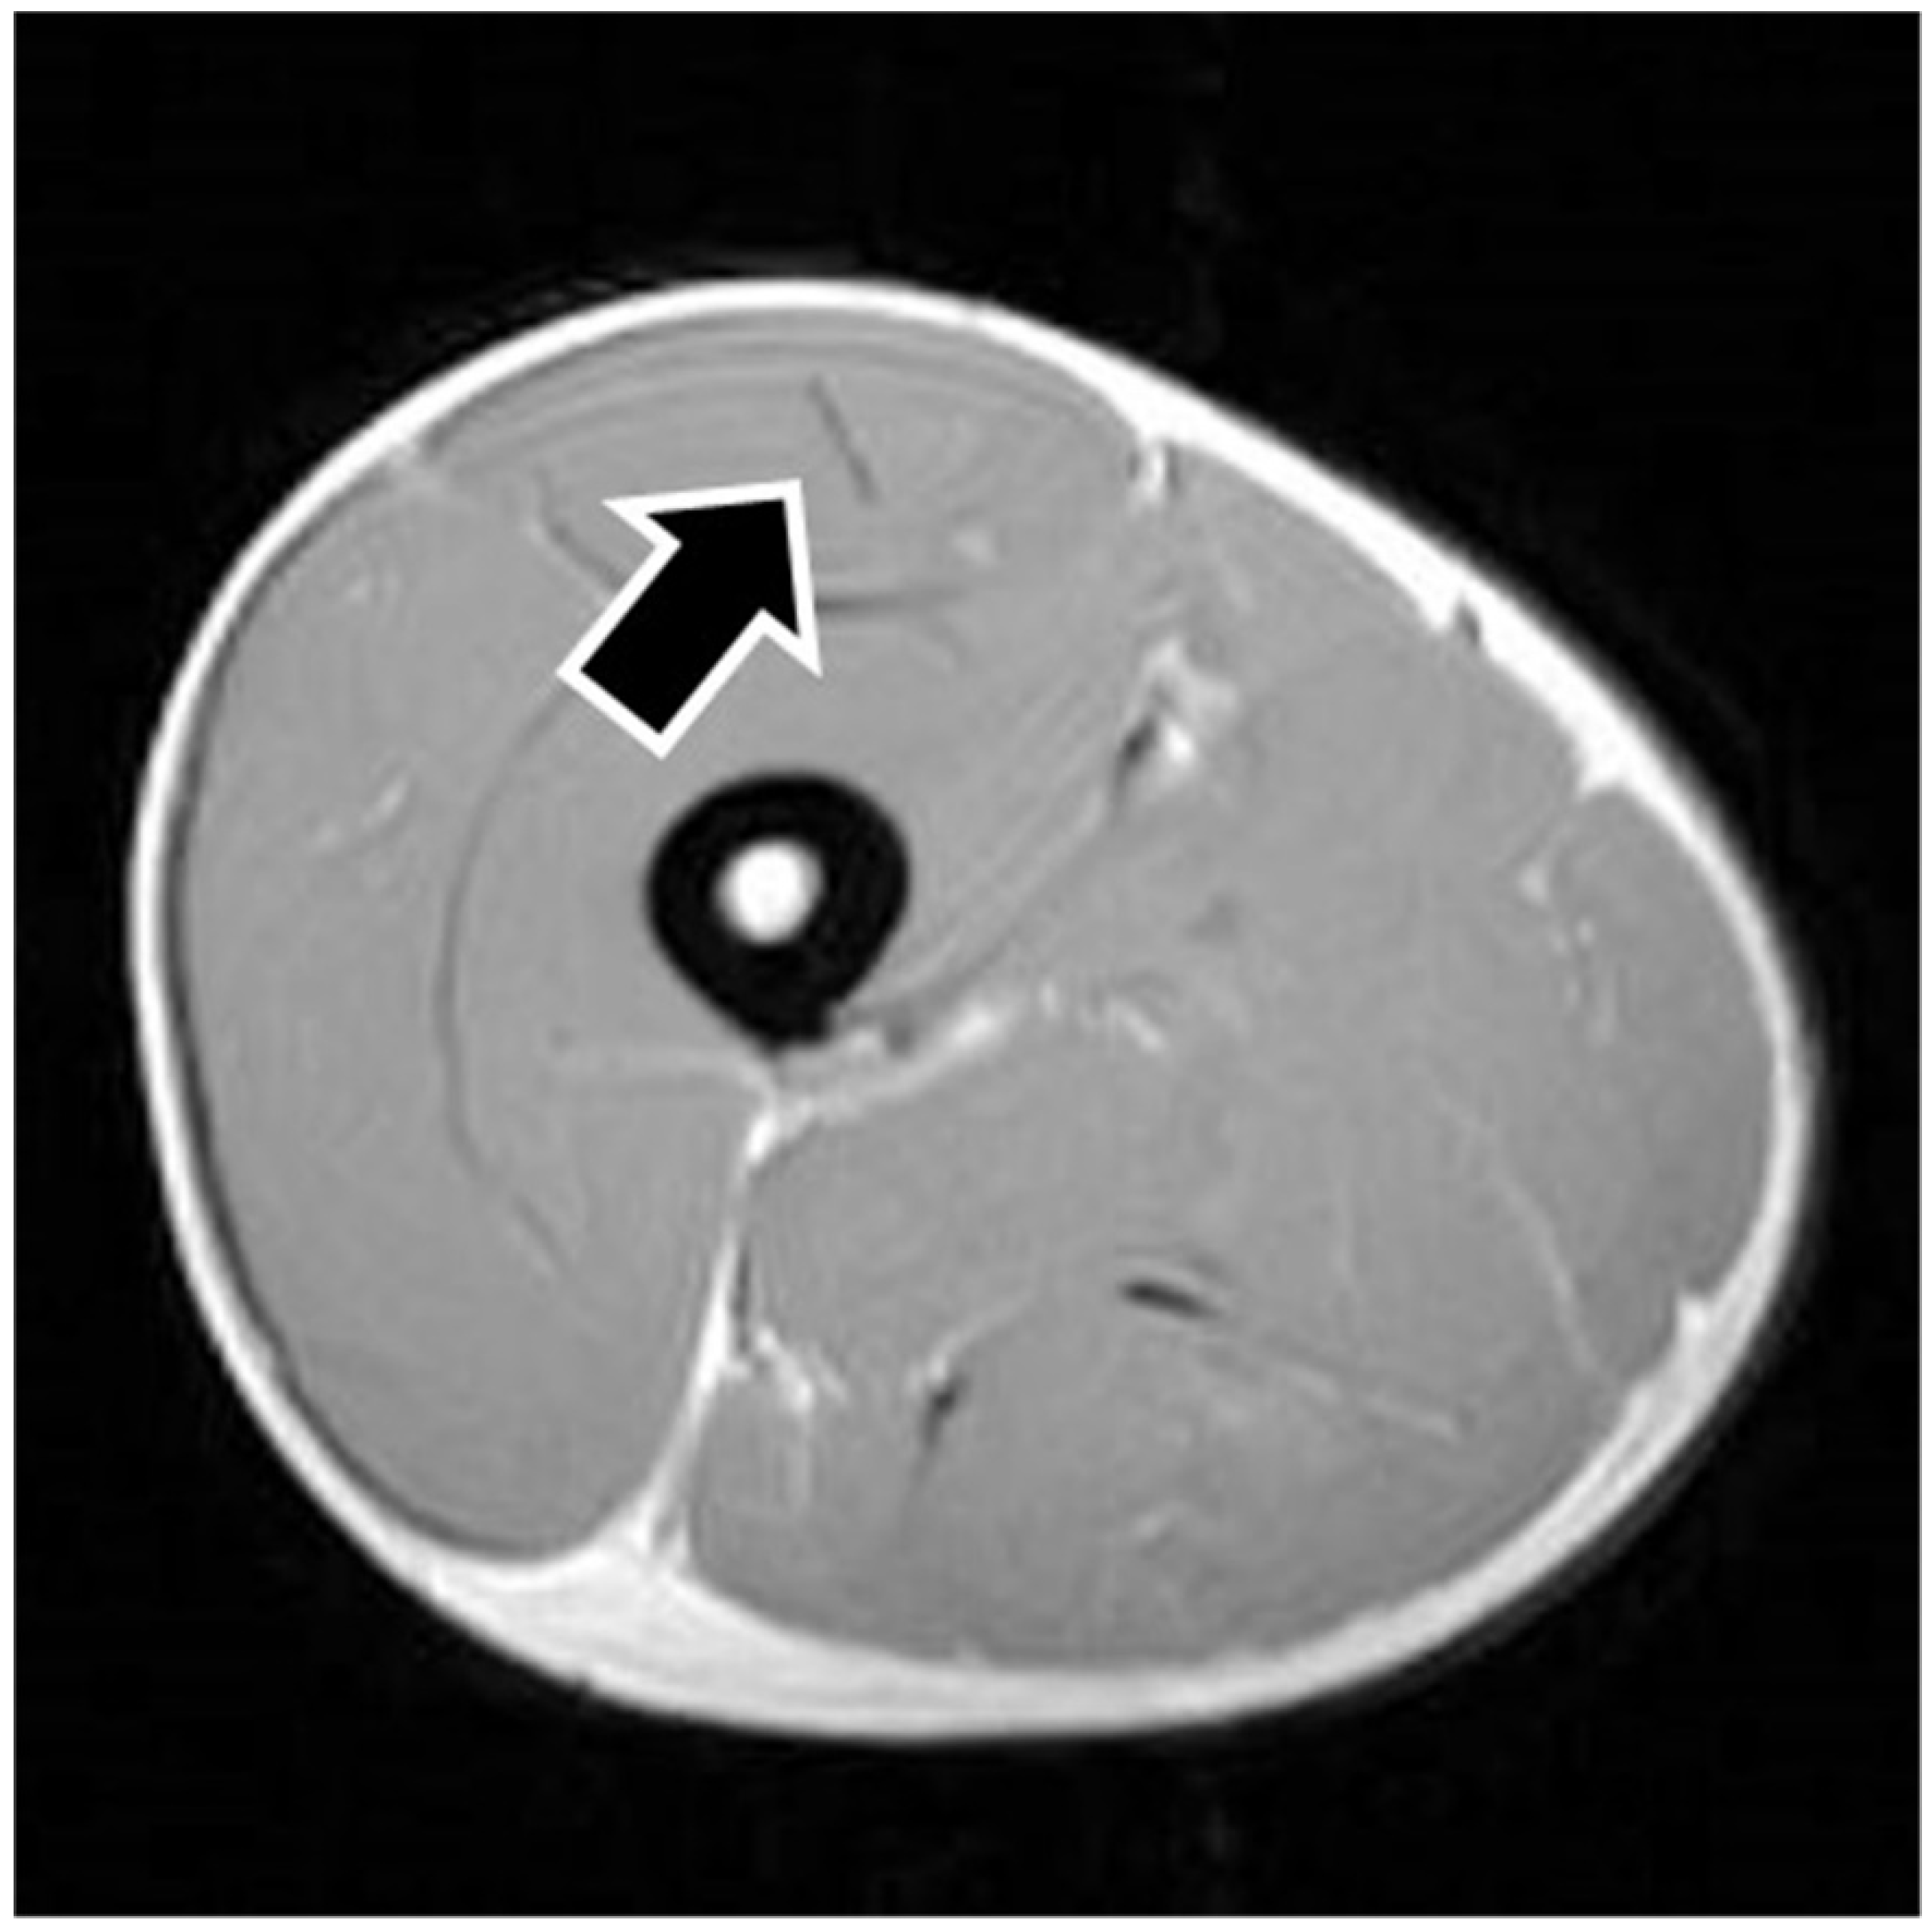

MRI findings are shown in Table 1. In eight of the RF strain injuries, a low signal area was noted in the central tendon (Figure 2). In four of the RF strain injuries, a low signal area was noted in the myofascial junction of the RF (Figure 3). In four of the RF strain injuries, the axial T1-weighted image did not show a low signal (Figure 4). The longitudinal range of the injured region in the 12 RF that showed a low signal area in MRI was approximately 8.8 cm (range, 4–17 cm). When the injured part was limited to the central tendon, the longitudinal range of the injured region was approximately 10.5 cm (range, 5–17 cm).

The MRI of a grade 1 strain is of a feathery appearance. Hemorrhage and fluid around the central tendon greatly suggest an acute grade 2 strain. In chronic or healing RF strains, there may be a fibrous encasement of the central tendon, characterized on MRI as T1 and T2 linear low signal around or adjacent to the central tendon [7]. The MRI showed a low signal area in this study so that the central tendon injured RFs were speculated as grade 2.

Figure 2. Pseudocyst of the central tendon. The figure shows an example of central tendon injury. The axial T1-weighted image shows a low signal surrounding the central tendon (black arrow), representing fibrous encasement.